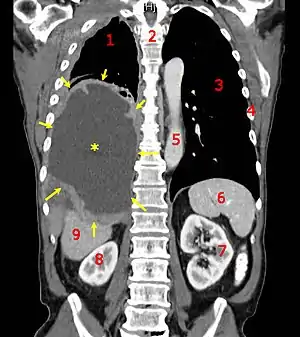

Diagnóstico

A maioria dos cânceres são inicialmente reconhecidos por causa de seus sintomas e sinais ou através de exames. Nenhum dos dois leva a um diagnóstico definitivo, que geralmente requer a opinião de um patologista. Pessoas com suspeita de câncer são investigadas com exames médicos. Estes geralmente incluem exames de sangue, radiografia, tomografia computadorizada, endoscopia, entre outros.[64]